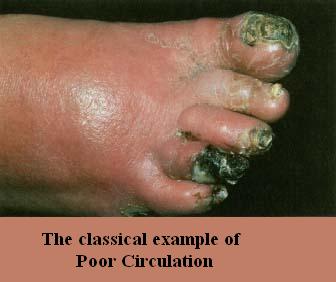

Poor circulation develops in the blood, lymph,

synovial and electrical

network, usually a combination of all 4. When this happens nutrients along

with their healing powers cannot find their way to where they are needed and the critical wastes are not

removed with poor circulation. In the case of electrical problems, nerve

damage results and this is addressed below. Nerve damage can have a very

serious consequence on parts of your body that may not be close to the area of

question. The brain being the nerve center of the body for one.

We believe and have written extensively on it that problems such as in the

knees, can create foreign materials that can wind up in your brain, hence

Alzheimer's. Could you think of a better reason to put your nose to the

grindstone?

Deterioration in the knee area is a logical happening as we age. The

feet, legs and knees in particular are a complex mechanism that of course moves and flexes and being in the lower

extremities where a series of arteries, veins, nerves and lymph fluids and check

valves moving up the legs to rid the wastes that accumulate, have quite a chore

as we age. Therefore these areas easily become deficient in adequate

circulation (again blood, lymph and electrical) to have nutrition and

wastes handled efficiently in and out of the area. You have to be brain

dead if you look at that diagram to the left and not believe that circulation is

not going to play an important role in the health of your lower extremities.